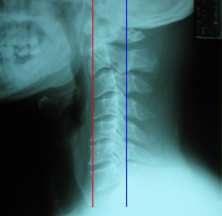

거북목 /일자목 / 목뼈의 후만 (역c자형 목)

정상적으로 인체의 중심중력선은 어깨의 중심과 귀를 동시에 통과해야 하는데 목이 전체적으로 앞으로 빠져 나가면 거북목이 형성됩니다. 이 때 정상적인 경추 만곡을 유지 할 수도 있지만 대부분 만곡이 소실되면서 일자목화 되거나 심하면 후만(뒤로 볼록한 형태) 을 형성하기도 하고 과도하게 전만(앞으로 볼록한 형태)이 되기도 합니다